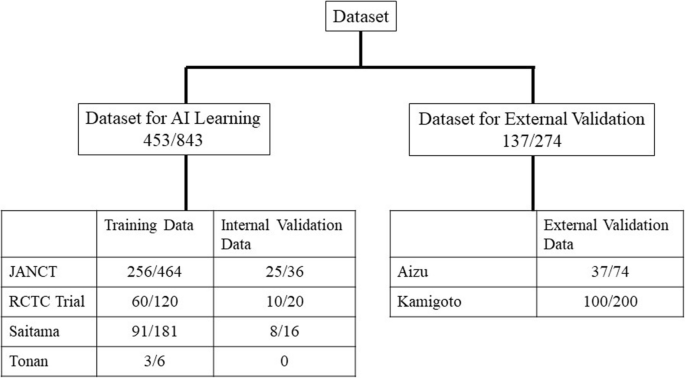

Lesion location and size were evaluated during colonoscopy and a large-scale database including a dataset for AI learning and external validation was created. The DICOM data used as training data and internal validation data (total 453 patients) for this study were colorectal cancer screening test data from two multicenter joint trial conducted in Japan and data from two institutions. External validation data (137 patients) were from other two institutions. Lesions were categorized into ≥6 mm, 6 to 10 mm, and ≥10 mm. During this study, we adopted a neural network structure that was designed based on the faster R-CNNs to detect colorectal lesion. The sensitivity of detecting colorectal lesions was verified when one and two positions were integrated.

The DICOM data of CT colonography were used to create a large-scale database, design an AI algorithm, and perform validation. To protect patient privacy, only image data, lesion information, sex, CT device (multidetector CT with at least 16 rows), slice thickness, and imaging position were used. The Strengthening the Reporting of Observational Studies in Epidemiology guidelines were followed during this study (Fig. 1). The research period spanned from October 2019 to August 2023, and the DICOM data used as training data were collected prior to this period. These data included screening tests from a multicenter joint trial conducted in Japan to validate the accuracy of CT colonography (Japanese National CT Colonography Trial) [15], data from another multicenter joint trial aimed at reducing the dose of intestinal cleansing agents while validating accuracy (Reduced-Laxative CT Colonography Trial) [16], and clinical data from Saitama Prefectural Cancer Center (Saitama) and Tonan Hospital (Tonan). The collected data were randomly divided into training and validation datasets. Table 1 shows the breakdown of the training data, including patient information, CT equipment used, and lesion size. During the present study, images obtained in one position were defined as one CT series; however, many images were obtained in two positions. In this study, we adopted the criteria used in previous research and defined lesions measuring 6 mm or larger as target lesions [3, 17]. Specifically, all target lesions were lesions ≥ 6 mm, and we categorized them into two groups: 6–10 mm and ≥ 10 mm. In most cases, the slice thickness was ≤1.0 mm. Although lesions ≥6 mm were included as targets in this study, the majority measured ≥10 mm. All lesions were pathologically confirmed to be adenomas or adenocarcinomas.

Study overview. The number of patients and series are shown for the AI training dataset and the external validation dataset, which were obtained from different institutes. The differences between the number of patients and the number of series are attributable to the fact that two CT examinations were performed per patient in two positions. AI: artificial intelligence; CT: computed tomography; JANCT: Japanese national CT colonography trial15; RCTC Trial: reduced-laxative CT colonography trial16.

Fig. 1 shows the numbers of patients and CT series in the AI learning dataset (training dataset and internal validation dataset) and external validation dataset. The AI learning datasets collected from the two previously published multicenter trials performed in Japan and the two aforementioned facilities were randomly divided into a training dataset used for AI training and an internal validation dataset that was used to validate the training results and there were no cases in each dataset that have been analyzed more than once. The external validation datasets of the two facilities of Fukushima Medical University Aizu Medical Center (Aizu) and Nagasaki Kamigoto Hospital (Kamigoto) were not used for AI learning.